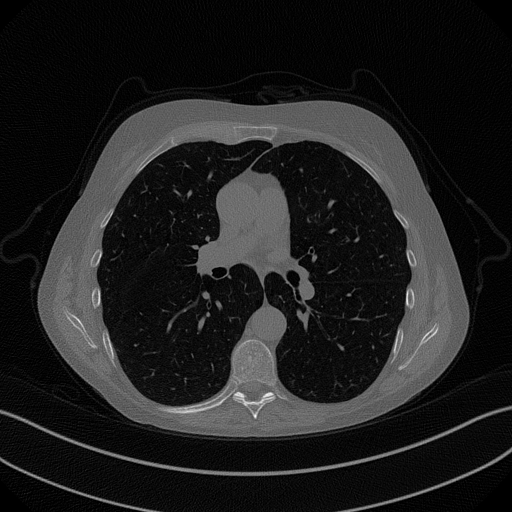

As real patient images, we have downloaded the widely used AAPM Low Dose CT Grand Challenge data set by the Mayo Clinic [35]. The considered images are 512×512512512512\times 512 pixel reconstructions of human abdomen, computed from full-dose acquisitions. In Figure 2 we depict one image with two zooms-in highlighting areas with different anatomical structures, such as pulmonary details, sections of ribs and low-contrast inter-costal muscles. In all the experiments reported in 5.1, we have used the images from the data set as ground truth xGTsubscript𝑥𝐺𝑇x_{GT} references. Coherently, we simulate the tomographic projections of the ground truth images, according to a 2D fan-beam geometry, and we add to the sinograms white Gaussian noise with 102superscript10210^{-2} noise level. To address sparse-view CT reconstructions, we considered two different protocols: the first one is a full angular acquisition with 1-degree spaced projections (we call it P360,360subscript𝑃360360P_{360,360} in the following); in the second one the scanning trajectory covers 180180180 degrees and computed only 606060 projections (it is labelled as P180,60subscript𝑃18060P_{180,60}).

Figure 2: A ground-truth image from the Low Dose Mayo data set, with two zoomed crops on regions with different anatomical structures.